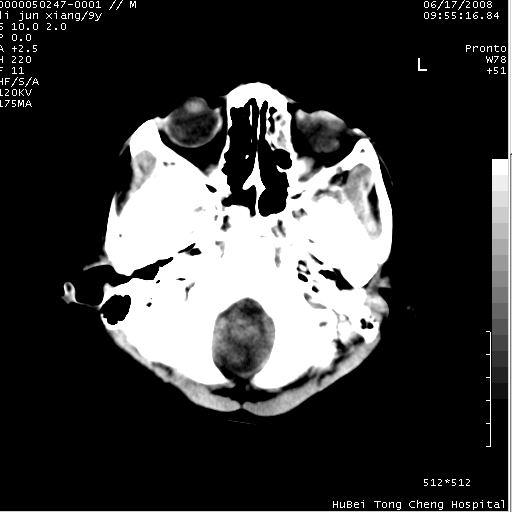

患儿 男,9岁。既往有“脑积水,脑萎缩?”病史(无影像检查资料),现无明显不适。其家长要求ct检查。

颅脑ct轴位平扫(层厚、层距均为10mm),图像如下: